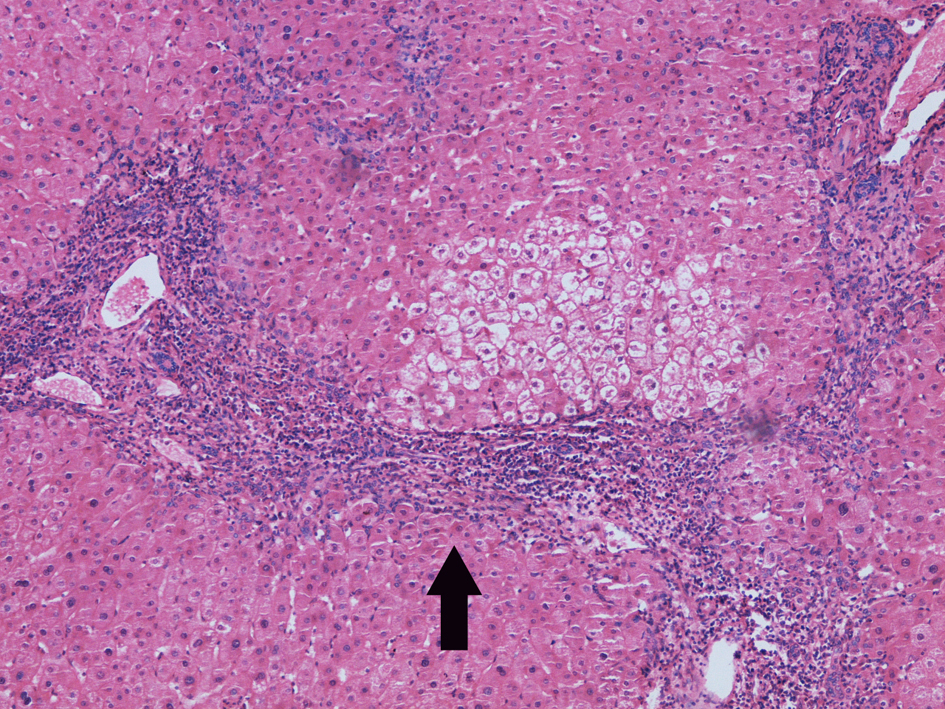

3.Chronic active viral hepatitis